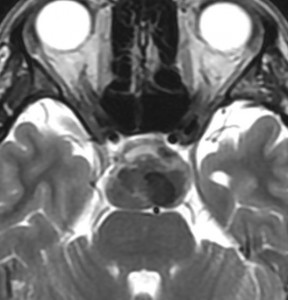

典型的な神経腸嚢胞 neurenteric cyst

左のT2強調画像で等信号,中のT2*で高信号,右はCISS画像です。

T1強調画像では,のう胞周囲の高信号の部分は半固体で,中心部の高信号はドロドロの粘液でした。基本的にガドリニウム増強はされません。まれに薄い膜状に一部が増強されることがあります。

境界明瞭は袋状の腫瘍です。椎骨動脈や脳底動脈を包み込むようにふくらんでいます。